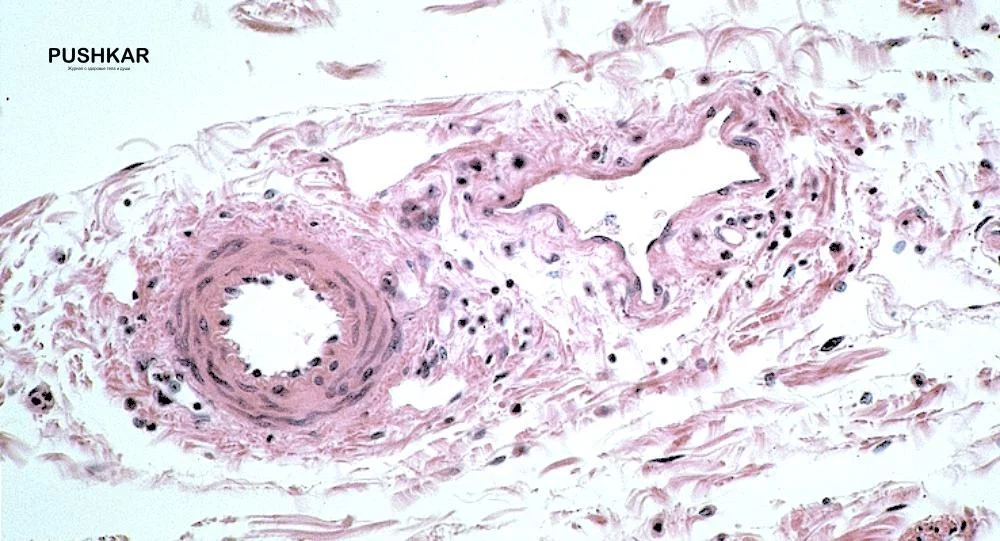

Фолликул яичников. Световая микроскопия, увеличение 200х.